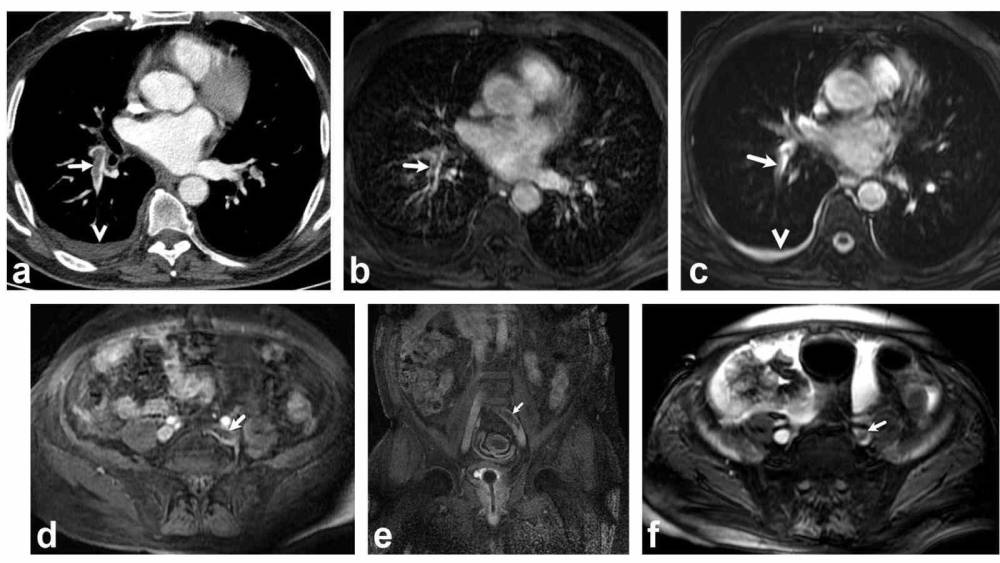

Bir dönem Denizli Tekden Hastanesinde de çalışan ve çalışmalarına ABD’de devam Dr. Nevzat Karabulut ve ekibinin yaptığı, British Journal of Radiology dergisinde yayımlanan "Diagnostic performance of contrast-enhanced and unenhanced combined pulmonary artery MRI and magnetic resonance venography techniques in the diagnosis of venous thromboembolism" başlıklı araştırmada manyetik rezonans (MR) yöntemi kullanılarak hem akciğer damarlarının hem de pıhtının kaynağı olan bacak toplardamarlarının aynı anda, tek bir incelemede değerlendirilebileceği gösterildi. Toplam 44 hastanın incelendiği çalışmada elde edilen sonuçlar oldukça dikkat çekti.

Kontrastlı MR yöntemi, hastaların tamamında akciğer embolisini doğru şekilde tespit ederken; kontrastsız MR yöntemi de yüksek doğruluk oranına ulaştı ve önemli ölçüde güvenilir sonuçlar verdi. Bu bulgular, radyasyon içermeyen MR yönteminin pıhtı hastalığını saptamada güçlü bir alternatif olduğunu ortaya koydu. Özellikle Radyasyon riskinin daha önemli olduğugenç hastalarda ve gebelerde MR’ın güvenli ve etkili bir seçenek olabileceği vurgulandı.

Dr. Karabulut’un bu çalışması, 2025 yılında yayımlanan kapsamlı bir meta-analizde önemli bir uluslararası dergide atıf aldı. Toplam 2 bin 611 hastanın yer aldığı bu meta-analizde Dr. Karabulut ve ekibinin yaptığı MR çalışması da bulundu. Meta-analiz sonuçlarına göre, geleneksel V/Q sintigrafisi (nükleer tıp yöntemi) ile yapılan incelemelerde tanı konulamayan vakaların oranı yaklaşık yüzde 34,7 olarak bulundu. Yani her üç hastadan birinde sonuç net olmayabiliyordu. Buna karşılık MR temelli yöntemlerde tanı konulamayan oran yalnızca %3,31 olarak rapor edildi. Bu oran, MR tekniklerinin çok daha net ve yorumlanabilir sonuçlar verdiğini ortaya koydu.

Bir dönem Denizli Tekden Hastanesinde de çalışan ve çalışmalarına ABD’de devam Dr. Nevzat Karabulut ve ekibinin yaptığı, British Journal of Radiology dergisinde yayımlanan "Diagnostic performance of contrast-enhanced and unenhanced combined pulmonary artery MRI and magnetic resonance venography techniques in the diagnosis of venous thromboembolism" başlıklı araştırmada manyetik rezonans (MR) yöntemi kullanılarak hem akciğer damarlarının hem de pıhtının kaynağı olan bacak toplardamarlarının aynı anda, tek bir incelemede değerlendirilebileceği gösterildi. Toplam 44 hastanın incelendiği çalışmada elde edilen sonuçlar oldukça dikkat çekti.

Kontrastlı MR yöntemi, hastaların tamamında akciğer embolisini doğru şekilde tespit ederken; kontrastsız MR yöntemi de yüksek doğruluk oranına ulaştı ve önemli ölçüde güvenilir sonuçlar verdi. Bu bulgular, radyasyon içermeyen MR yönteminin pıhtı hastalığını saptamada güçlü bir alternatif olduğunu ortaya koydu. Özellikle Radyasyon riskinin daha önemli olduğugenç hastalarda ve gebelerde MR’ın güvenli ve etkili bir seçenek olabileceği vurgulandı.

Dr. Karabulut’un bu çalışması, 2025 yılında yayımlanan kapsamlı bir meta-analizde önemli bir uluslararası dergide atıf aldı. Toplam 2 bin 611 hastanın yer aldığı bu meta-analizde Dr. Karabulut ve ekibinin yaptığı MR çalışması da bulundu. Meta-analiz sonuçlarına göre, geleneksel V/Q sintigrafisi (nükleer tıp yöntemi) ile yapılan incelemelerde tanı konulamayan vakaların oranı yaklaşık yüzde 34,7 olarak bulundu. Yani her üç hastadan birinde sonuç net olmayabiliyordu. Buna karşılık MR temelli yöntemlerde tanı konulamayan oran yalnızca %3,31 olarak rapor edildi. Bu oran, MR tekniklerinin çok daha net ve yorumlanabilir sonuçlar verdiğini ortaya koydu.